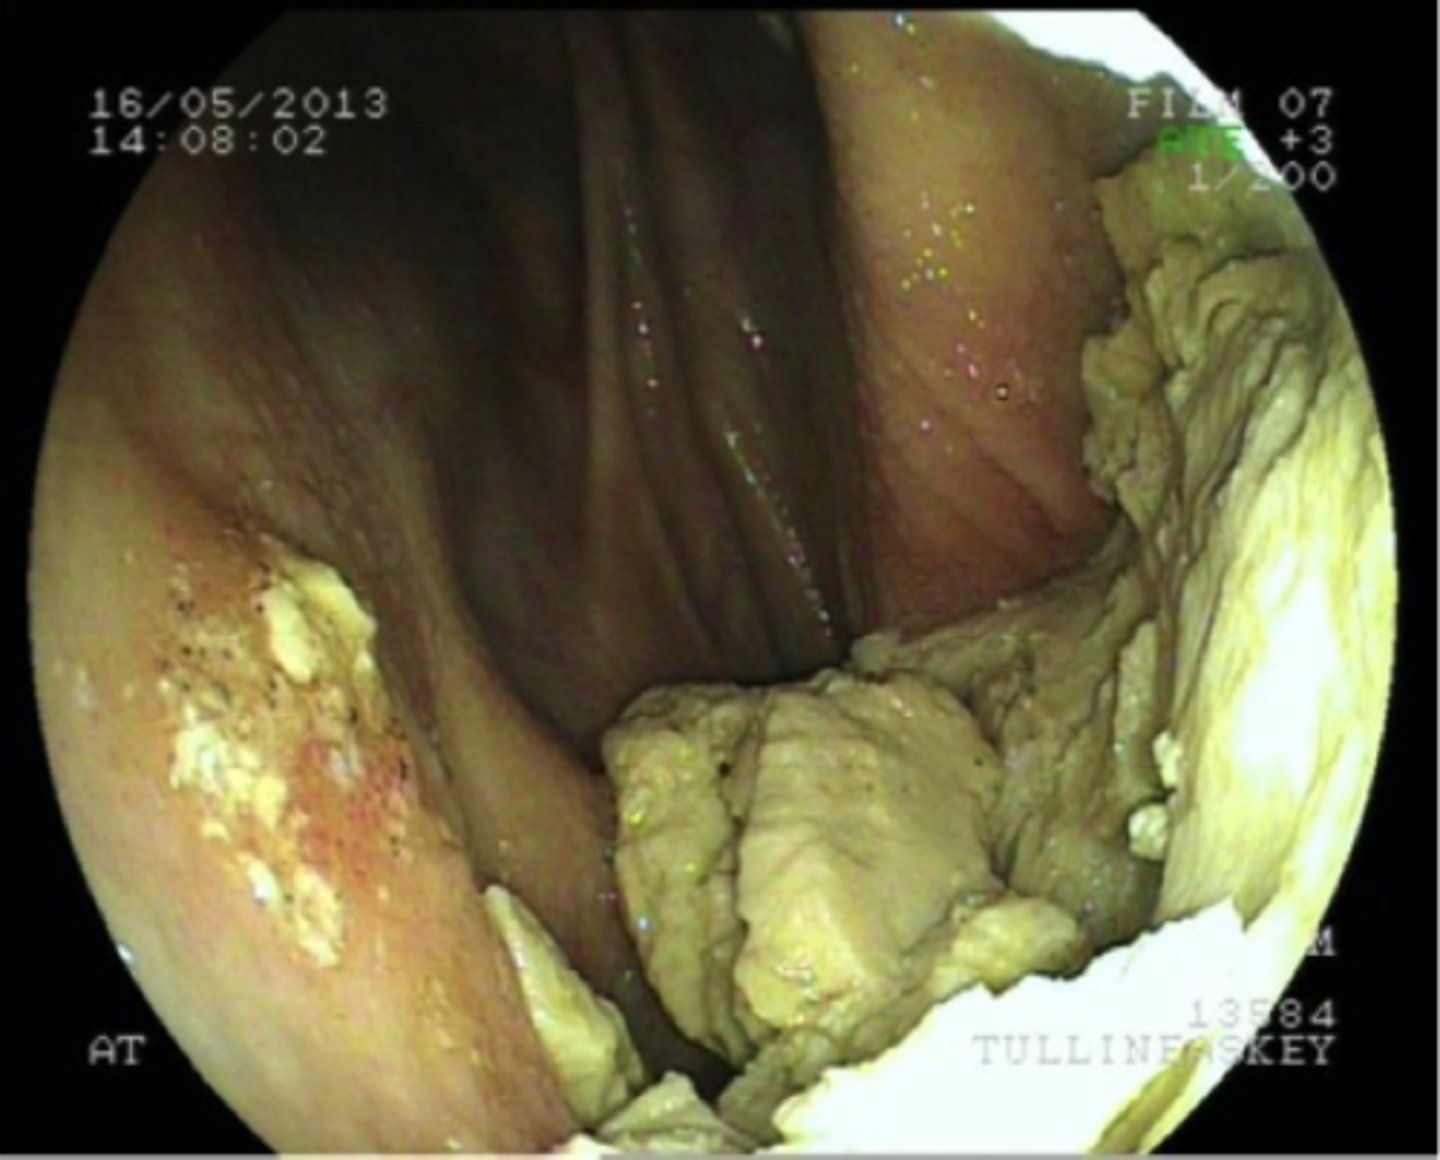

Non-strangulerende intestinal nekrose

En hest på 6 år har haft mild kolik og feber i nogle dage. Ved indlæggelsen på hospitalet diagnosticeres hesten med peritonitis og der foretages en eksplorativ laparotomi. Hvordan vil du karakterisere denne læsion i flexura pelvina?

- Strangulerende intestinal nekrose

- Non-strangulerende intestinal nekrose

- Non-strangulerende intestinal inflammation

- Strangulerende intestinal ischæmi

Trombo-embolisk infarkt

Ved en eksplorativ laparotomi på en hest med kolik og peritonitis, findes denne læsion på Flexura Pelvina. Hvad er den mest sandsynlige årsag til dette?

- Neoplasi

- Obstruktion

- Trombo-embolisk infarkt

- Colitis